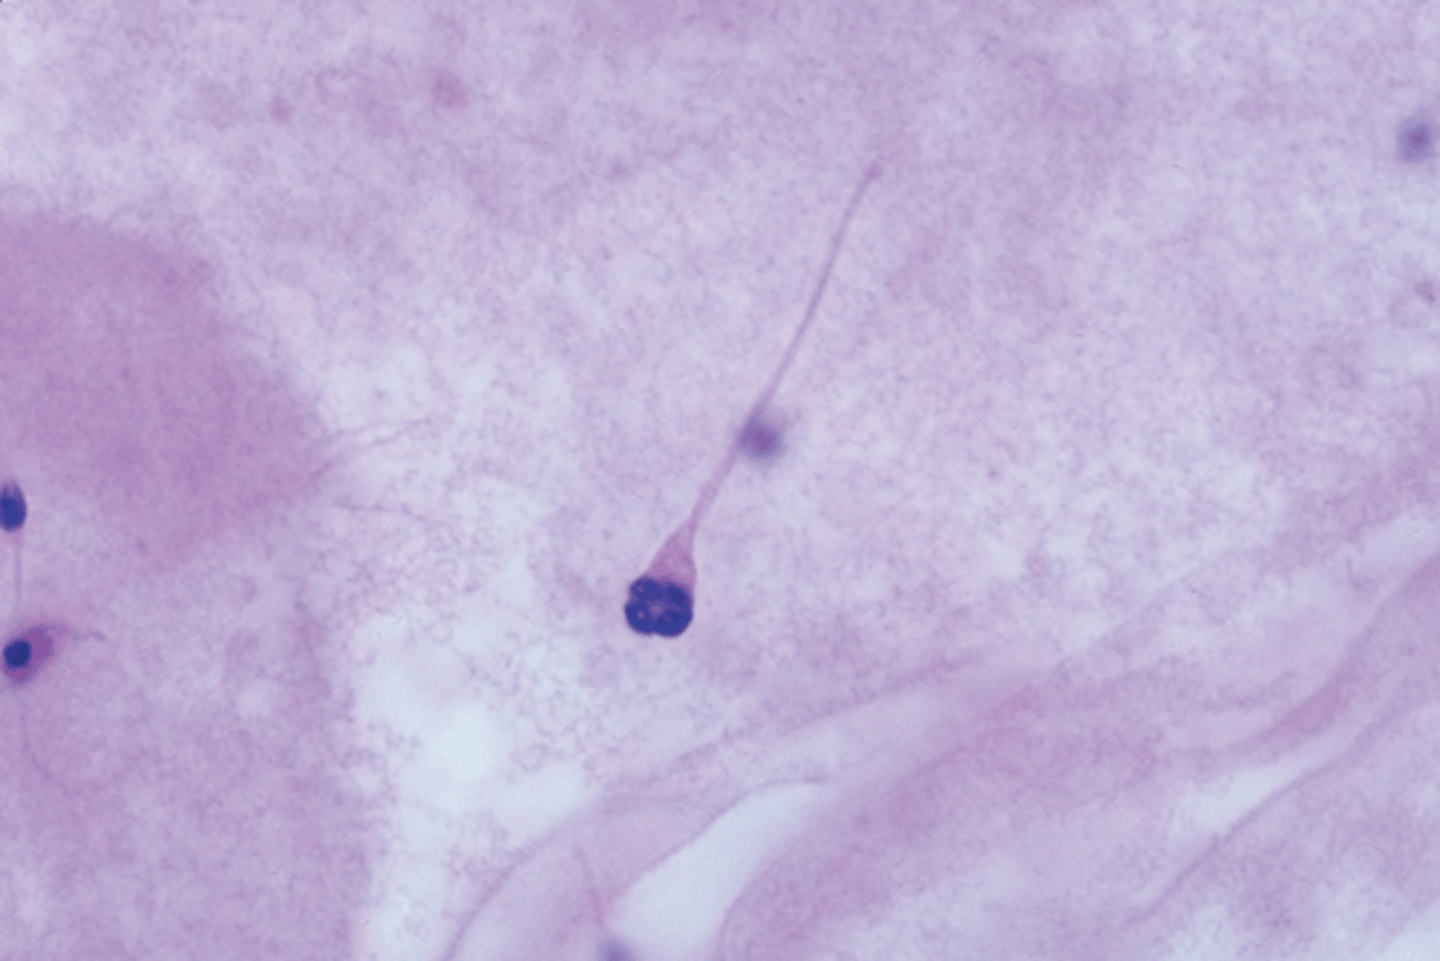

Amorphous head

"squished"

Coiled tail

Cytoplasmic droplet

Macrocytic head

Microcytic head

Pin head

Tapered sperm

Double head

Paired sperm

Tailed are twisted together

Double tail sperm